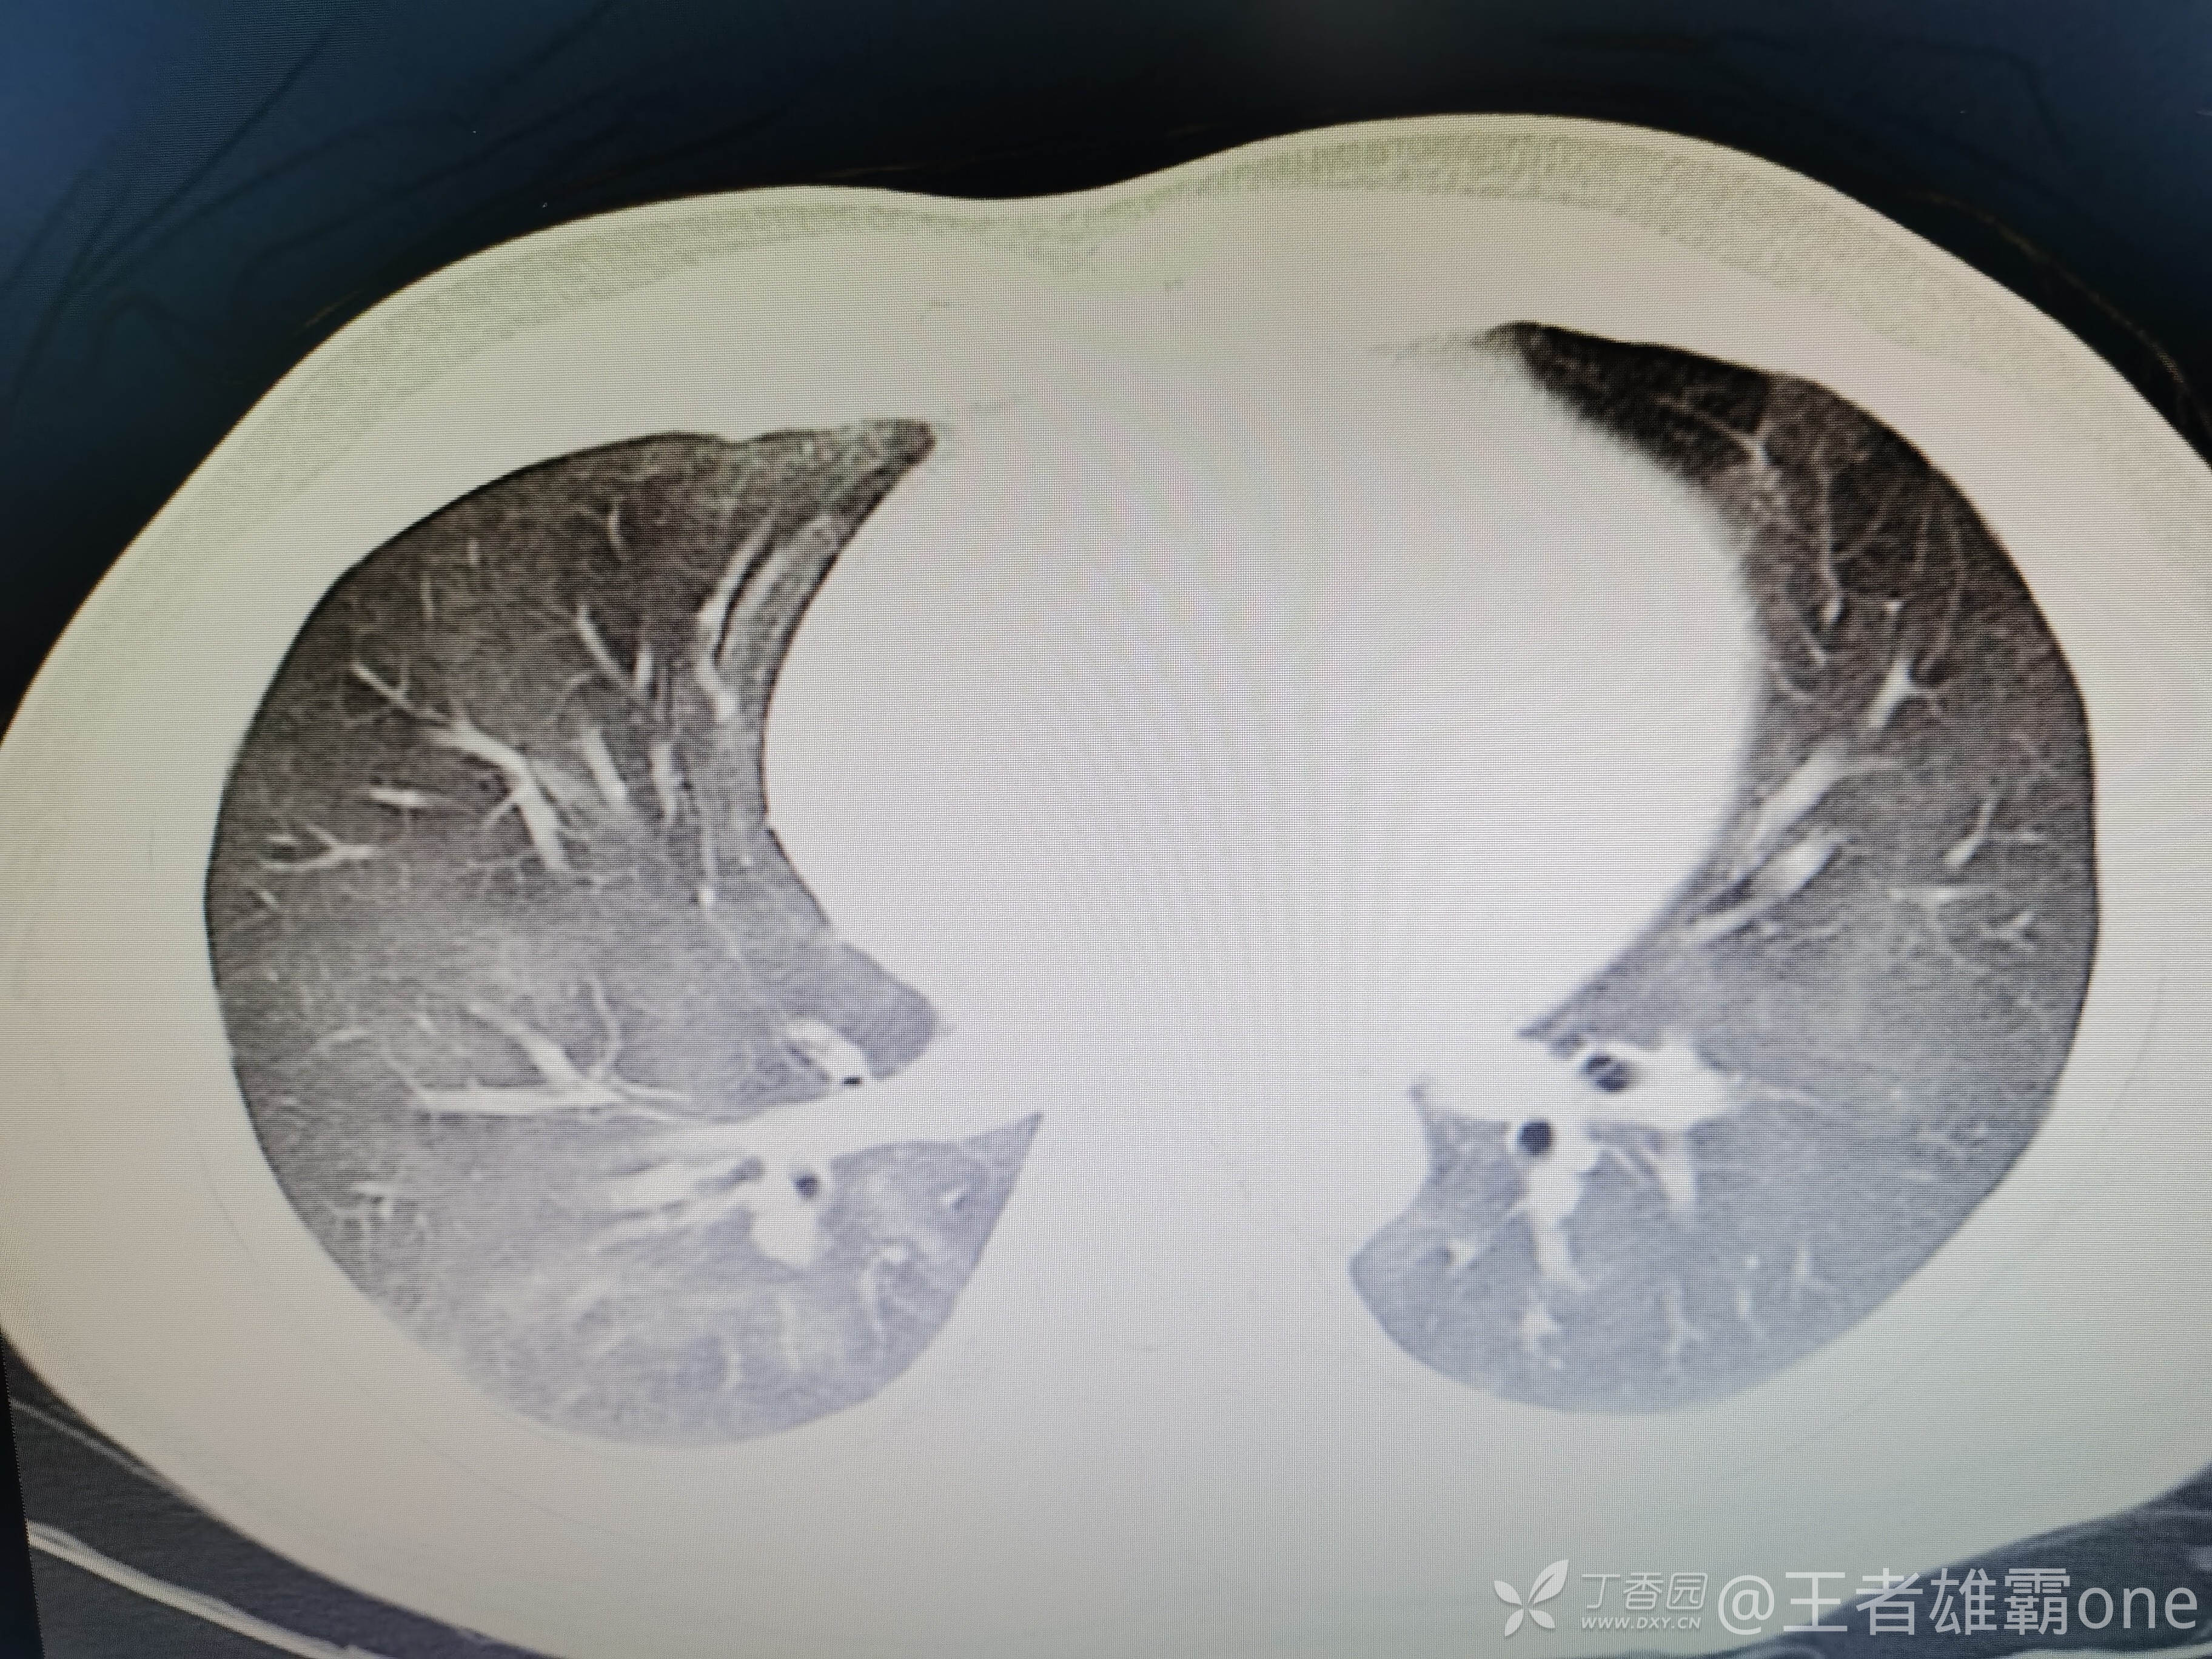

西门开心 推荐男,33岁,否认既往有心脏基础疾病,6-1受伤后急诊行右胫腓骨骨折固定术(术前胸部CT无明显异常,见后面视频前半部分),术后逐渐出现刺激性咳嗽、胸闷,无精神症状,无皮疹,无胸痛,无咯血等。6-6完善胸部CT、脑钠肽前体、心超等辅查,其中脑钠肽前体、心超无明显异常。复查的胸部CT见视频后半部分:

附几张CT图片: